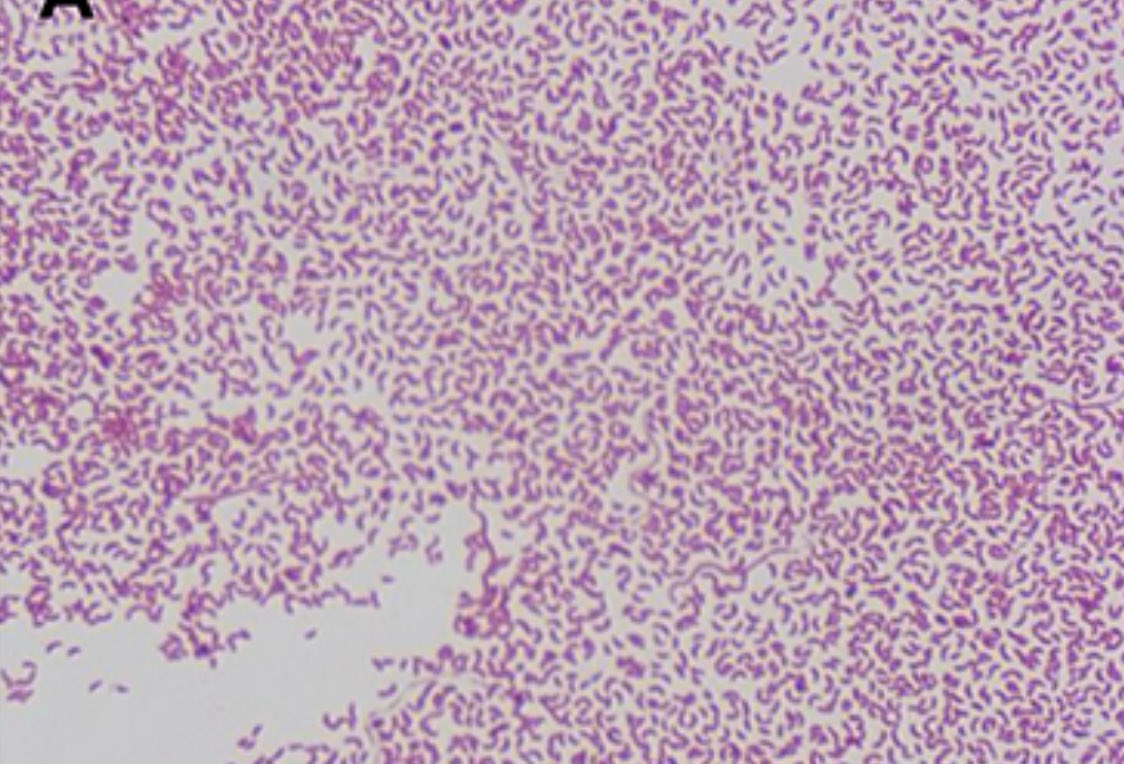

#idboardreview 60 yo garbage handler from Pakistan presents w/ fever, severe rice water diarrhea w/fishy odor, hypotension, metabolic acidosis, AKI. BC curvy gram neg rods. Dx? #meded #idmedEd #IDTwitter ImageImage

Vibrio #cholera curved gram neg rod, fecal oral, poor sanitation, severe watery diarrhea to death. Pics Ref dovepress.com/non-o1-non-o13…

vibrio #cholerae O1 and O139 serogroup are cause of epidemic cholera

Non-O1 & Non-O139 can cause isolated cases of usually mild gastroenteritis